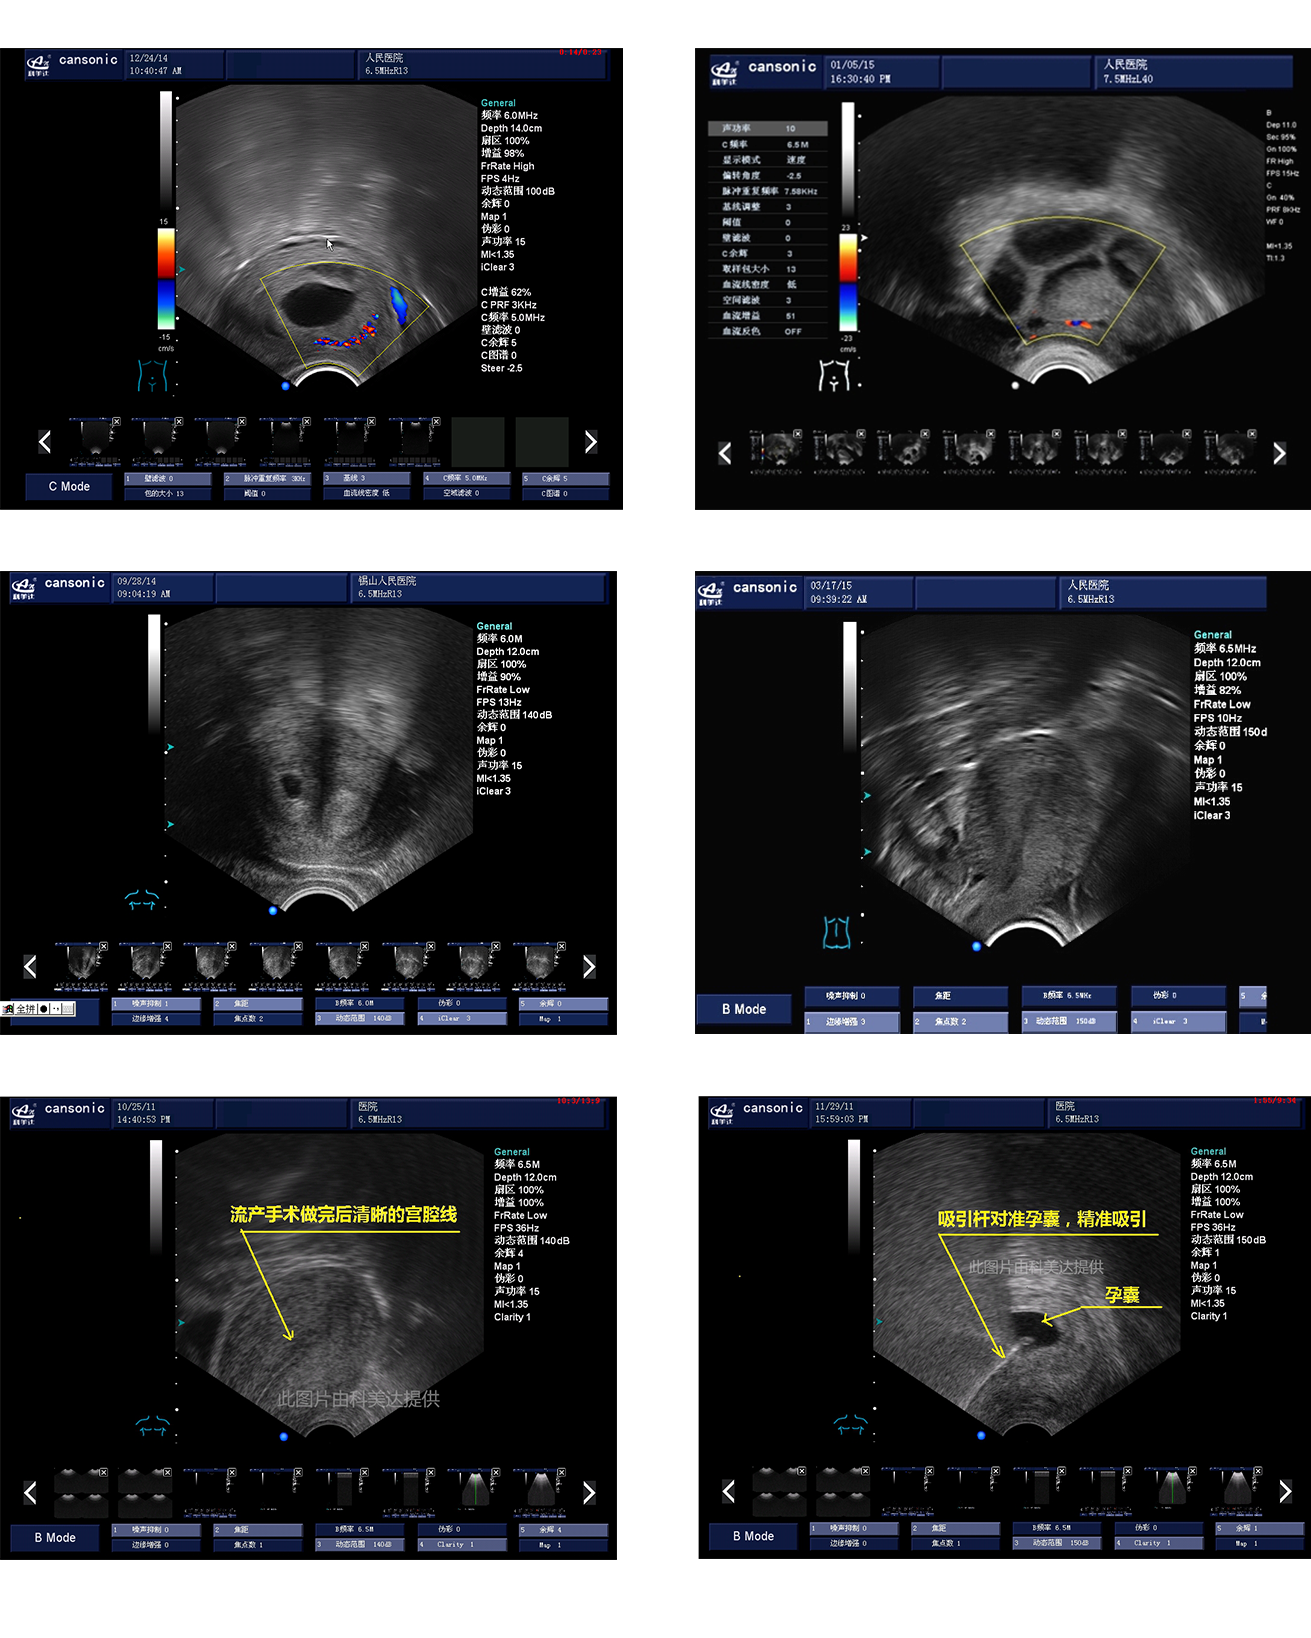

臨床圖示

1、薈萃前沿彩超技術(shù),使得超聲監(jiān)測(cè)與手術(shù)操作完美融合,實(shí)現(xiàn)宮腔手術(shù)的全程監(jiān)測(cè)

2、復(fù)合成像技術(shù),增強(qiáng)組織回聲,減少回聲失落,得到清晰、真實(shí)的手術(shù)影像

3、血流靈敏度高,清晰可見